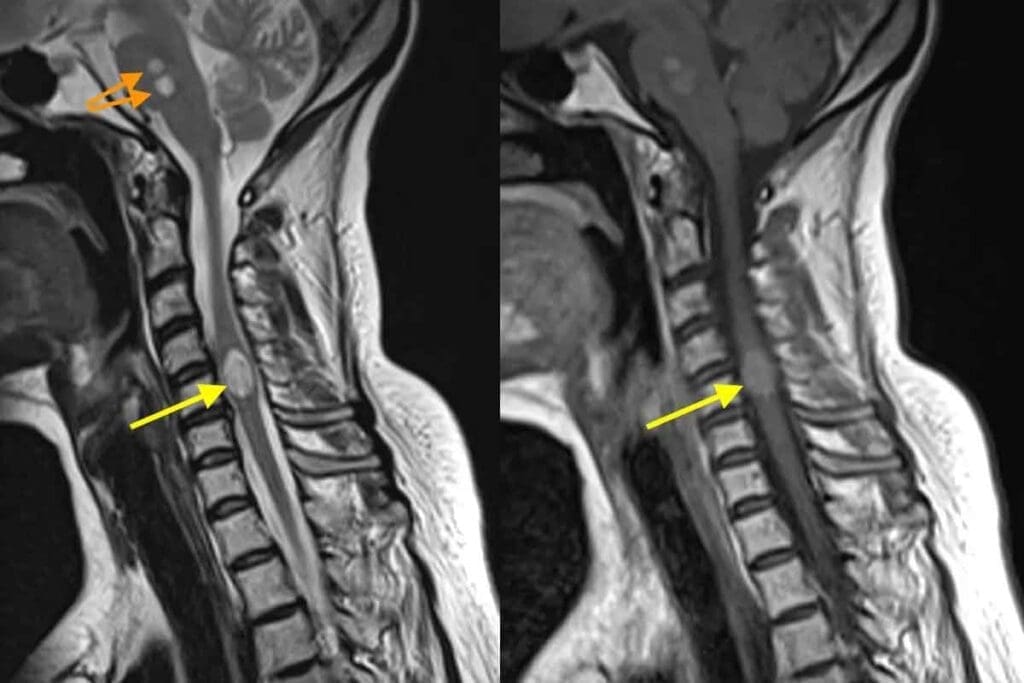

Imaging Modalities and Their Role

Imaging studies are key in diagnosing Ewing Sarcoma. MRI and CT scans help see how big the tumor is and if it has spread. MRI is great for checking soft tissue and how the tumor affects nearby areas.